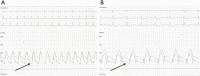

Figure 7

Simultaneous recording of aortic and pulmonary arterial tracings in an 18-year-old girl with ASD and severe PHT (A) before and (B) after balloon occlusion of the defect. Note significant drop in pulmonary artery pressures (arrows) after temporary balloon occlusion. ASD, atrial septal defect.